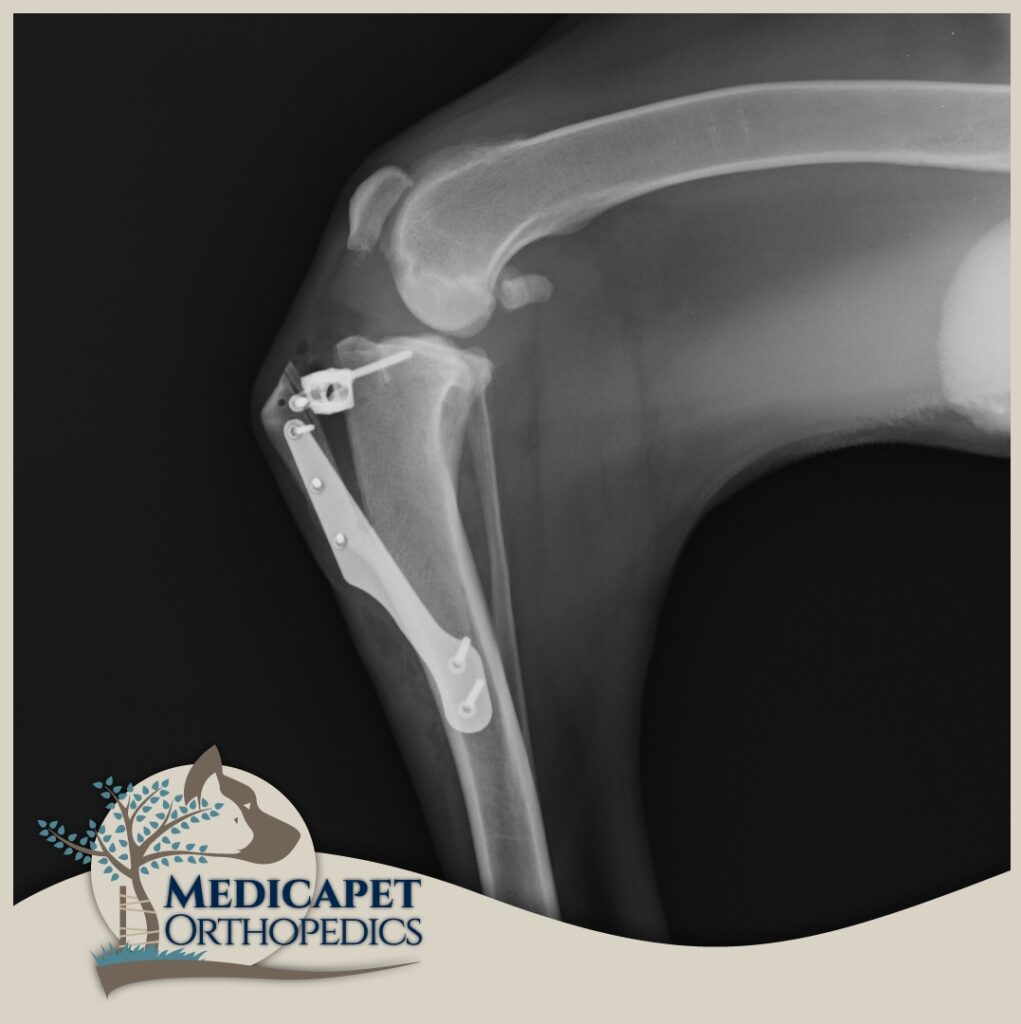

TTA – Tibia’nın ilerletilmesi

Bu ameliyat, TPLO ile aynı prensibi izler ve ön çapraz bağı gereksiz kılan bir geometrik ve biyomekanik bir değişikllik meydana getirir. TTA’nın ardındaki matematiksel prensipler, TPLO’nun ardındakilerden daha karmaşıktır; ancak temel prensip, quadriceps kas grubundan gelen çekiş yönünün değişmesinin, femur kemiğinin tibial plato eğiminden aşağı doğru kayma eğilimini nötralize eden diz eklemi boyunca bir kuvvet üretmesidir. Aslında, hem TTA hem de TPLO, tibial platoyu düz patellar tendona dik hale getirmeyi ve bunu yaparken femur kemiğinin tibia eğiminden aşağı doğru kayma eğilimini nötralize etmeyi amaçlar. Patellar ligament hasarı olan hastalarda TTA tekniği uygun olmayacaktır. Çünkü TTA tekniğini uygularken bu ligamentin çekme kuvvetinden faydalanılır.

Bu ameliyat, tibianın üst kısmında dairesel bir kesi oluşturulmasını ve kemikteki önceki eğim artık mevcut olmayana kadar plato segmentinin döndürülmesini içerir. Daha sonra kemik, kemik plakası ve vidalar kullanılarak bu yeni pozisyonda sabitlenir. Böylece femurun tibia üzerinde uygunsuz şekilde kayması engellenmiş olur. Hassas ölçümler ve kusursuz el maniplasyonu gerektirdiği için tecrübeli ve ehil cerrahlar tarafından uygulanmalıdır.